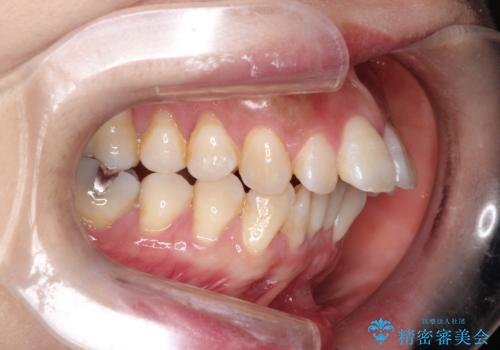

インビザラインによるガタつきの治療 クロスバイトの改善

- 中等度の叢生(ガタつき)のため、インビザラインによる非抜歯治療を計画します。